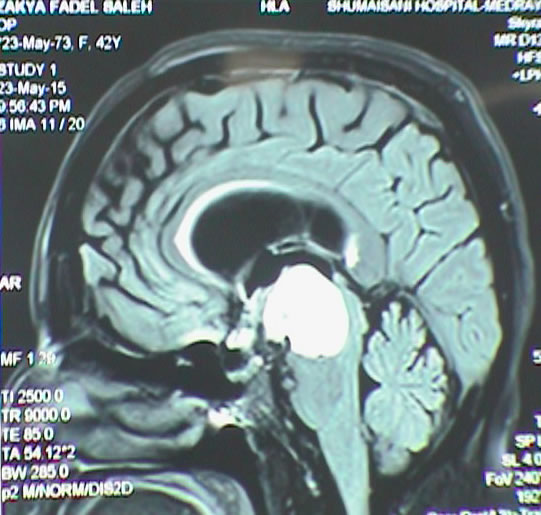

Below, showing a case with posterior third ventricular anaplastic ganglioma in 30 years old patient to whom intraoperative MRI with spectroscopy, SWI and MRA were performed twice to confirm the total resection of the tumor. See fig-1-7.

Fig-1: Choline distribution showing a small nidus of possible malignant character befor attacking the lesion.

Fig-8: MRI showing the cystic craniopharyngeal cyst pushing the mesencephalon inferior.